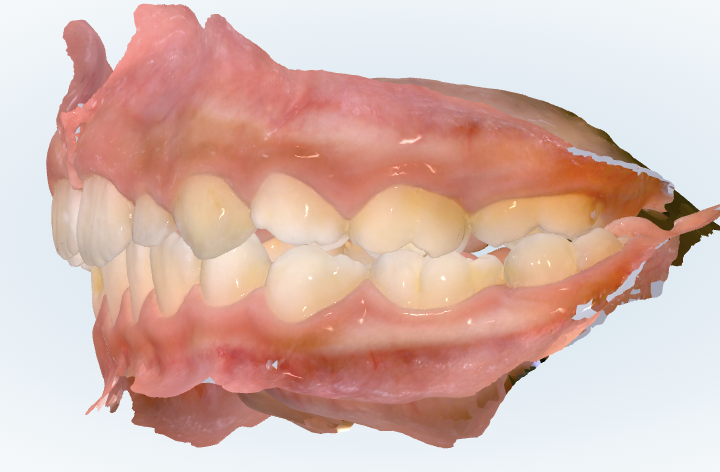

初診時の画像診断

一方で、奥歯の噛み合わせを左右で見ると、右と左でズレ方が違うのが気になります。

右側はそこまで悪くないんですが、反対側を見るとズレが少し大きいです。

これは歯だけの問題というより、下顎が少し左右にずれて噛んでいるつまり顎が偏位している可能性が高いです。

あと、噛み合わせが少し深めです。極端に深くて歯ぐきを傷つけているような状況ではないですが、成長を利用してこれ以上深くならないようにコントロールするのは大事なポイントです。